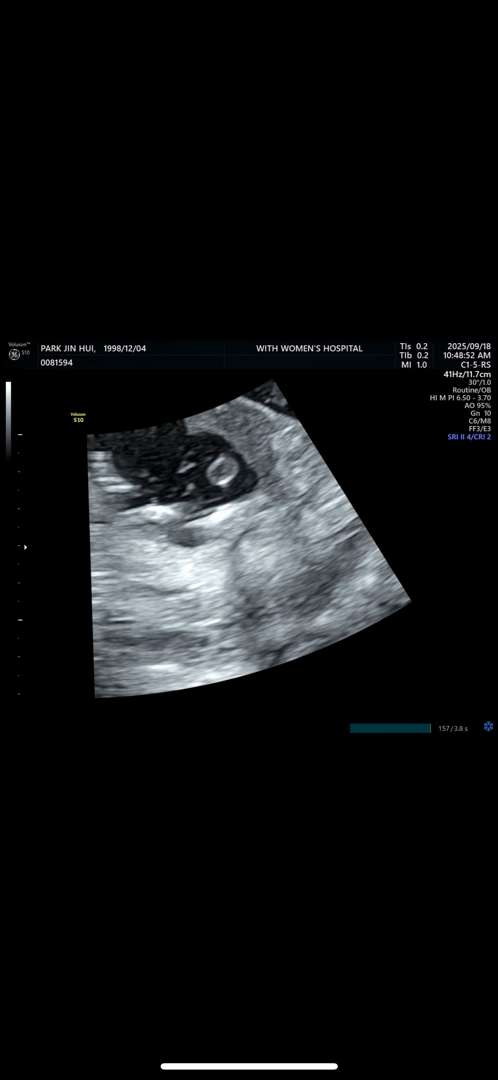

이정도면 딸 맞겟죠?

16주 4일인데요 이정도면 딸인거죠?